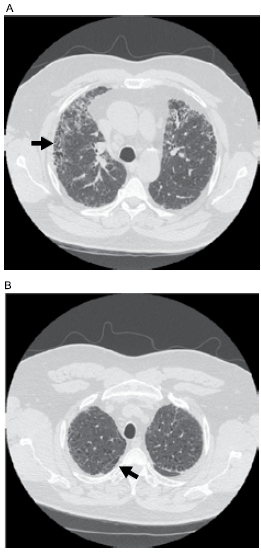

Paciente do sexo masculino, 78 anos, fumou durante 50 anos, tendo parado recentemente. Refere cansaço intenso aos pequenos esforços, associado à sibilância expiratória recorrente e faz uso de tiotrópio e formoterol com budesonida inalatórios. Relata tosse matinal recorrente com expectoração hialina em grande quantidade. Há uma semana, apresentou quadro compatível com infecção de vias aéreas superiores, com rinorreia, dor muscular e queda do estado geral. Refere que, desde então, apresenta piora da falta de ar e aumento na expectoração, que se tornou esverdeada. O exame físico de admissão revela: paciente em mal estado geral; taquidispneico e com tempo expiratório muito prolongado; ausculta pulmonar com sibilos inspiratórios e expiratórios difusos, associados a crepitações grosseiras em 1/3 inferior do hemitórax direito; asuculta cardíaca normal, com frequência cardíaca de 120 bpm; !$ SpO_2 !$ = 69% e PA = 110 x 60 mmHg. Realizada tomografia de tórax que se encontra ilustrada a seguir.

Os principais germes envolvidos na exacerbação infecciosa da doença pulmonar obstrutiva crônica são: